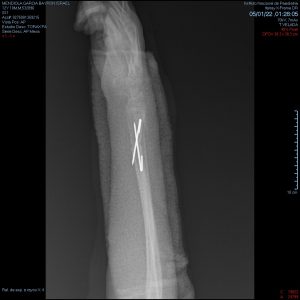

- Fracturas de antebrazo

- Fractura de radio y cubito

Fractura radiocubital